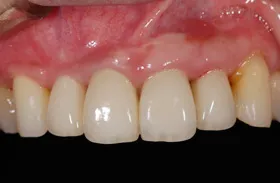

前歯欠損の為来院されたケース

■治療前

■治療後

治療のポイント

- 骨幅が狭い状態です。

- インプラントを埋めると同時に、骨を作る処置をさせて頂きました。

| 主訴 | 上顎の抜歯した箇所の機能障害・審美障害 |

|---|---|

| 治療方法 | 上顎の欠損部位に1本のインプラントを埋入し、同時に外科的治療で骨造成を行った |

| 治療期間 | 約1年 |

| 通院回数等 | 10回 |

| 費用 | 550,000円(税込) |

| リスク・副作用 | 外科的に骨を作る為、治療後に腫れることがある |